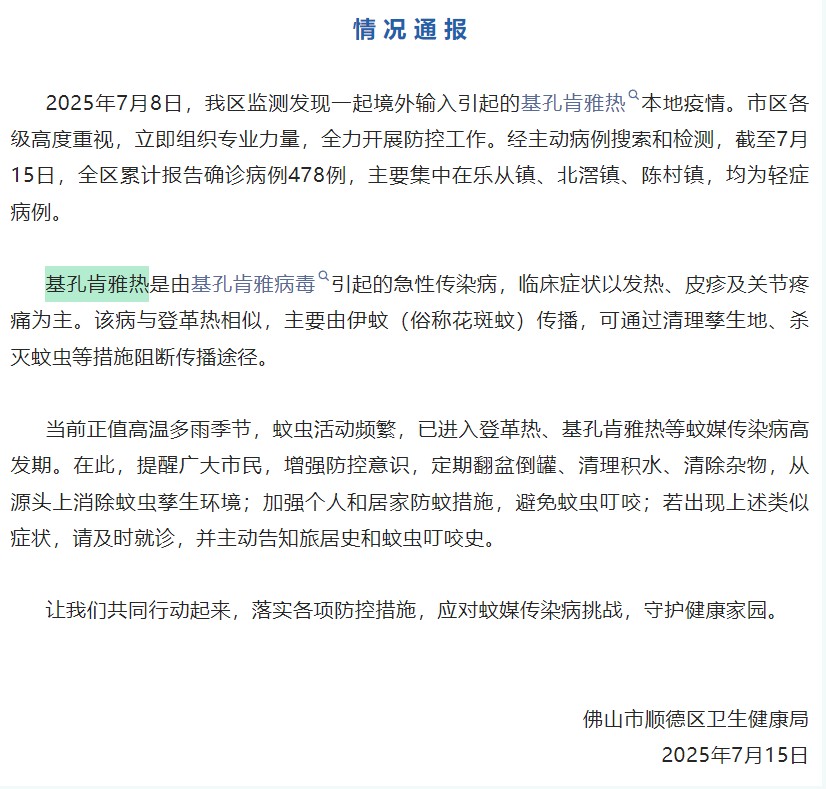

近日,佛山市順德區(qū)衛(wèi)生健康局發(fā)布情況通報:2025年7月8日,我區(qū)監(jiān)測發(fā)現(xiàn)一起境外輸入引起的基孔肯雅熱本地疫情。截至7月15日,全區(qū)累計報告確診病例478例,均為輕癥病例。

針對國內(nèi)出現(xiàn)基孔肯雅熱疫情,結(jié)合夏季蚊媒傳染病的傳播風險顯著增加,中國疾控中心也發(fā)布了健康提示,提醒公眾需重點防范經(jīng)伊蚊傳播的登革熱和基孔肯雅熱。

基孔肯雅熱(Chikungunya fever)是由基孔肯雅病毒(Chikungunya virus, CHIKV)引起、經(jīng)媒介伊蚊叮咬吸血傳播的一種急性傳染病。